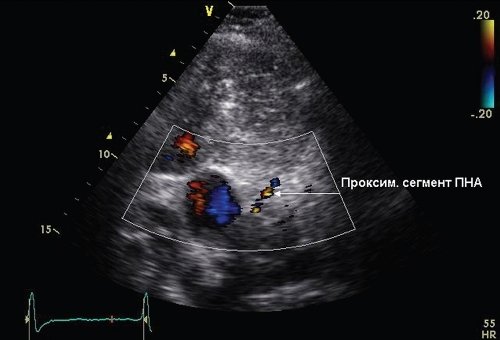

Визуализация проксимального и дистального отделов ПНА была выполнена при использовании второй тканевой гармоники и цветового допплеровского картирования, согласно методике M. Krzanowski и соавт. [4], R. Land и соавт. [14] и P.P. Dimitrow [2]. Проксимальный сегмент ПНА визуализировали из модифицированной апикальной позиции на промежуточном положении между поперечным сечением аорты на уровне клапана и 5-камерной позиции (рис. 1).

Рис. 1. Эхограмма проксимального сегмента ПНА из модифицированной апикальной позиции на промежуточном положении между поперечным сечением аорты на уровне клапана и 5-камерной позиции.

Первоначально осуществляли визуализацию КА в цветовом допплеровском режиме с уровнем цветовой шкалы 20 см/с, при достижении хорошей визуализации проксимального сегмента ПНА записывали в импульсном допплеровском режиме спектр коронарного потока. Визуализацию дистального сегмента ПНА осуществляли из апикальной позиции на уровне 4 камер или на промежуточной позиции между 4-й и 5-й камерами в цве товом допплеровском режиме при уровне цветовой шкалы 20 см/с (рис. 2).